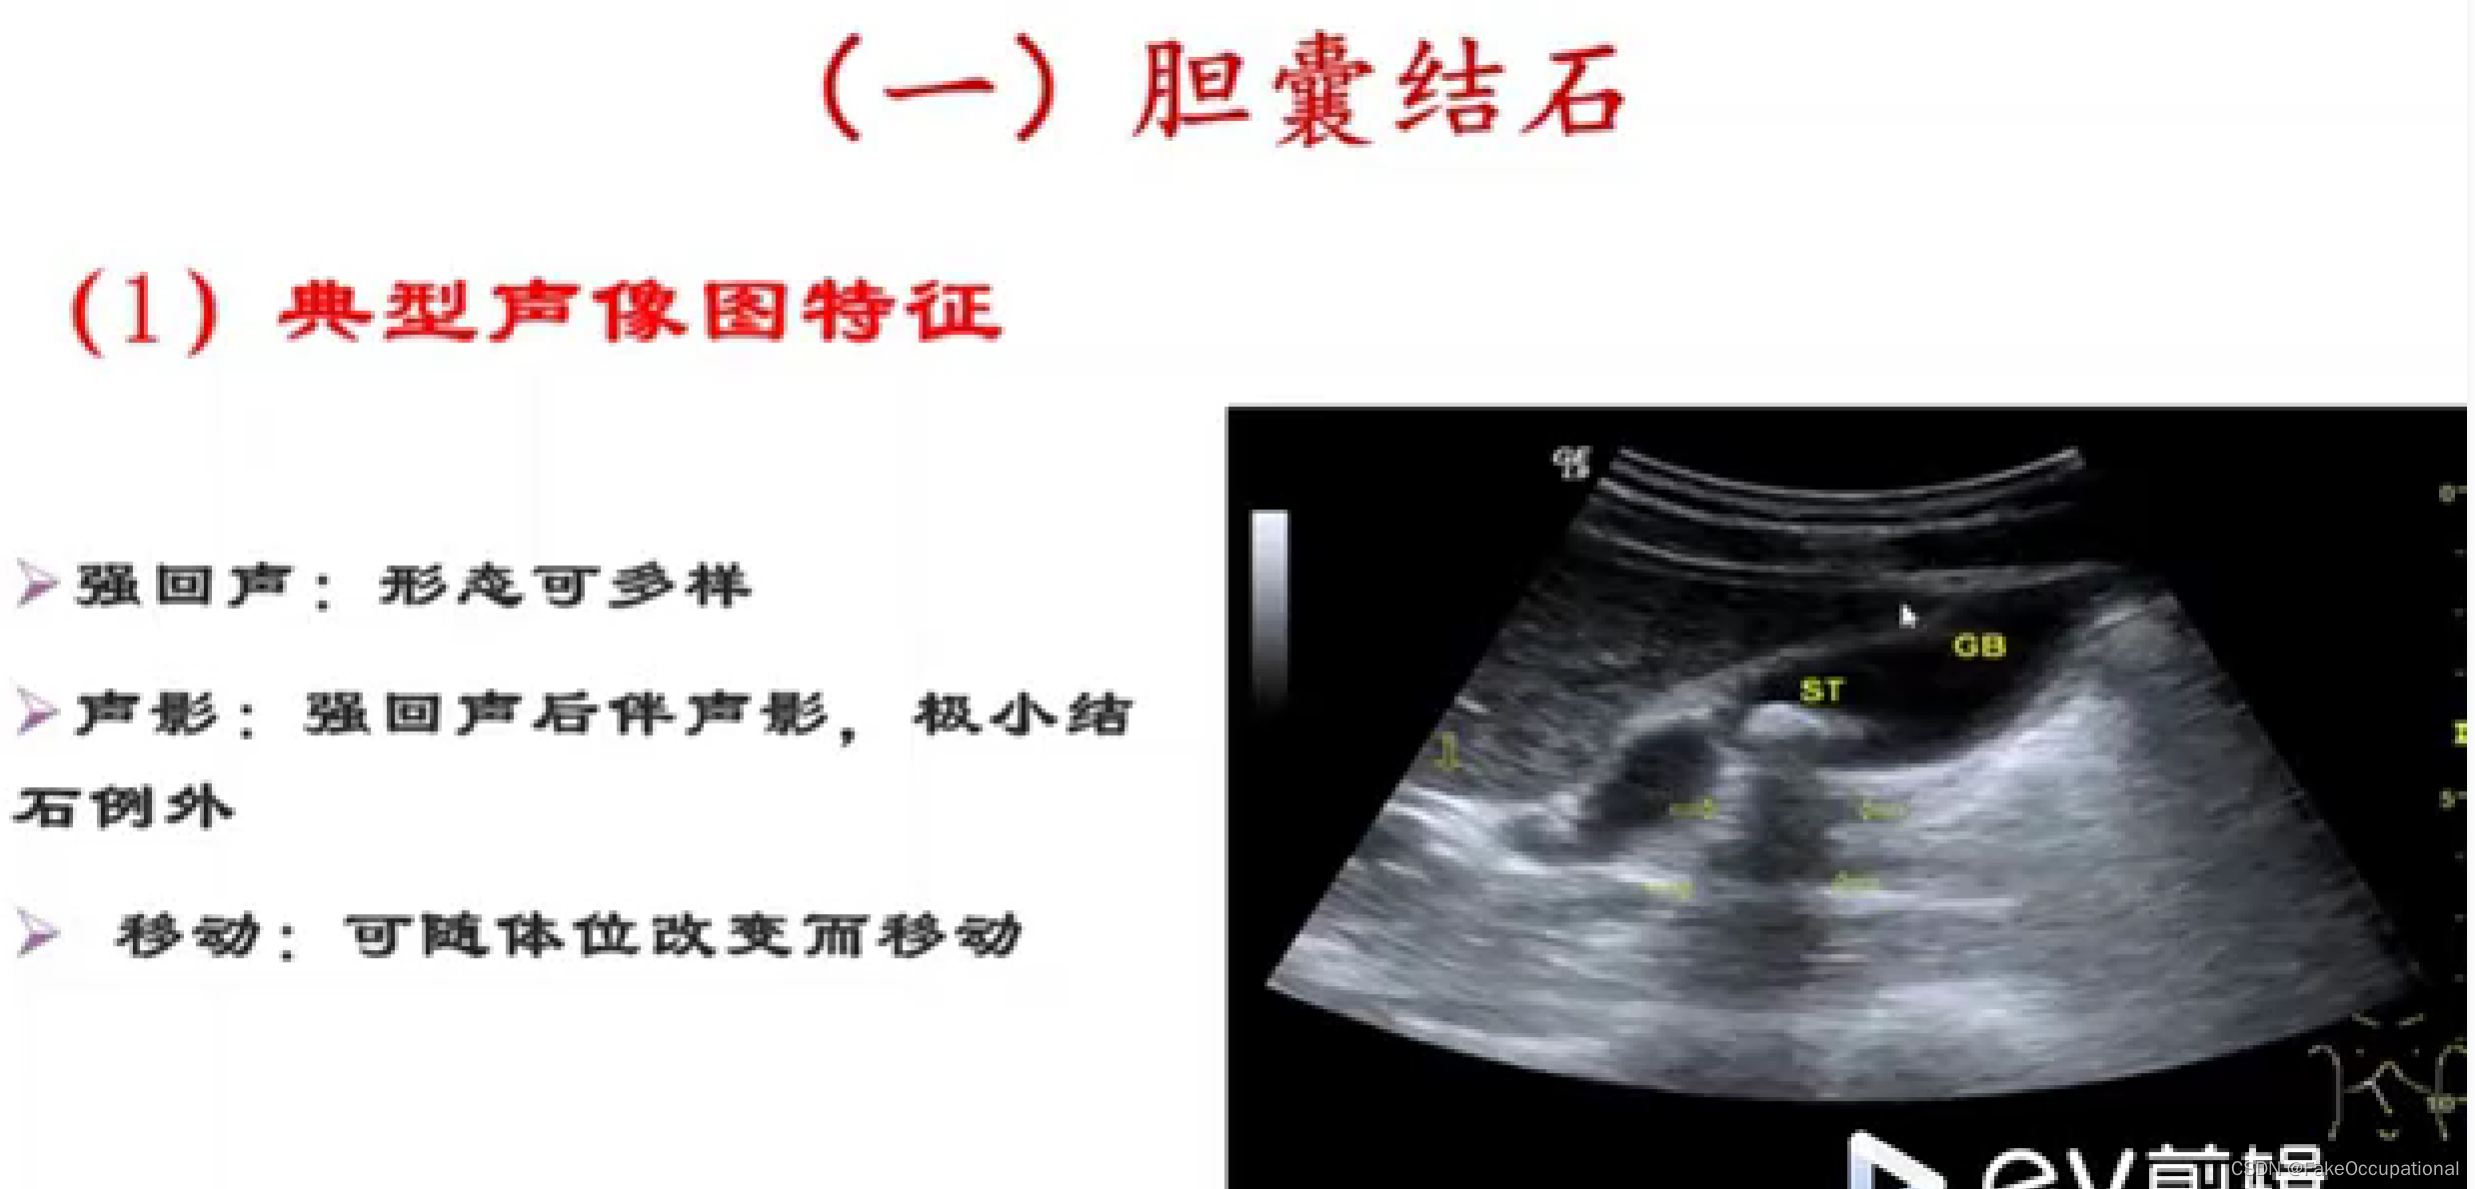

异常胆囊及胆管声像图